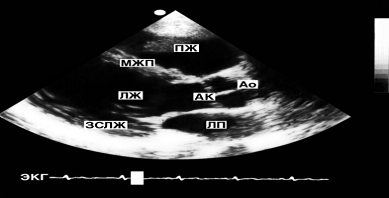

Рис. 3. Схема основных позиций одномерной эхографии структур сердца, расположенных вблизи его основания (позиция 1), в средней трети длины (позиции 2 и 3) и в области верхушки (позиция 4)

Во всех позициях отображаются передняя стенка правого желудочка и его полость, а в позициях 3 и 4 - межжелудочковая перегородка, полость левого желудочка и его задняя стенка, в позиции 1 визуализируются аорта, аортальный клапан (АК), полость левого предсердия и его задняя стенка (ЗСЛП), в позиции 2 - левое предсердие и митральный клапан. Дополнительные обозначения: I - генератор УЗ и приемник отраженных сигналов; II - передняя грудная стенка; III - сердце; IV - задняя грудная стенка.